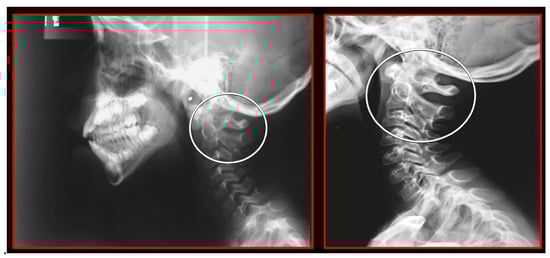

- Rocabado, M.; Gutierrez, R.; Gutierrez, M.F.; Gutierrez, M.J. Case report: Anterior open bite correction treatment by dental treatment and physical therapy through craniocervical mandibular and occlusal stabilization. Cranio 2021, 10, 1–6. [Google Scholar] [CrossRef]